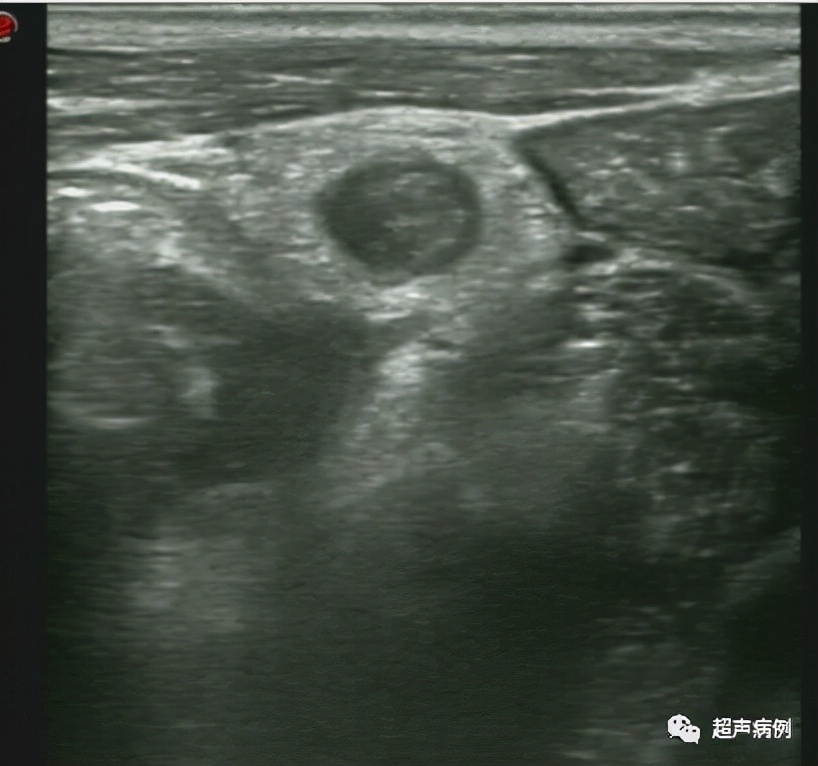

What Does Appendicitis Look Like On Ultrasound . — ultrasound is considered the imaging modality of choice for pediatric and pregnant patients where appendicitis is. Appendicitis is most commonly treated by. Acute appendicitis is the most common surgical emergency in children with higher incidence between. Ultrasound with its lack of ionising radiation should be the investigation of choice in young patients. — what does appendicitis look like on ultrasound? — acute appendicitis (aa) is a disease with a high prevalence, requiring rapid and accurate diagnosis to confirm or. ct is the most sensitive modality to detect appendicitis although its use should be limited because of the radiation dose. — an ultrasound or ct scan will usually show an enlarged appendix. — • ultrasound (us) should be the first imaging modality for diagnosing. — appendicitis is a frequent cause of abdominal pain. — the first steps are with the use of the appropriate imaging modality (us, ct and mri) to locate the appendix in abdominal cavity and to identify the features of appendicitis and its complications through specific imaging signs. by the end of this video, you'll be able to look at an ultrasound image and distinguish between a normal appendix and an inflamed one so that you can quickly identify and treat a case of appendicitis. — the most useful sign of acute appendicitis on ultrasonography is an outer appendiceal diameter of 6 mm or greater. While many cases of appendicitis are easy to diagnose clinically, a significant number need further workup. Symptoms may be atypical, and the appendix may not be.

— in a patient with undifferentiated right lower quadrant pain, appendicitis is often at the top of the. — • ultrasound (us) should be the first imaging modality for diagnosing. by the end of this video, you'll be able to look at an ultrasound image and distinguish between a normal appendix and an inflamed one so that you can quickly identify and treat a case of appendicitis. The appendix will be greater than 6 mm in outer diameter. Acute appendicitis is the most common surgical emergency in children with higher incidence between. Ultrasound with its lack of ionising radiation should be the investigation of choice in young patients. — an ultrasound or ct scan will usually show an enlarged appendix. Appendicitis is most commonly treated by. — acute appendicitis (aa) is a disease with a high prevalence, requiring rapid and accurate diagnosis to confirm or. — ultrasound is considered the imaging modality of choice for pediatric and pregnant patients where appendicitis is.

Acute Appendicitis On Ultrasound What Does Appendicitis Look Like On Ultrasound — the most useful sign of acute appendicitis on ultrasonography is an outer appendiceal diameter of 6 mm or greater. — what does appendicitis look like on ultrasound? ct is the most sensitive modality to detect appendicitis although its use should be limited because of the radiation dose. While many cases of appendicitis are easy to diagnose. What Does Appendicitis Look Like On Ultrasound.